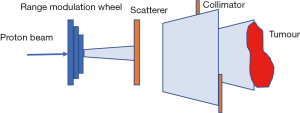

In passive scattering nozzle, a beam of protons passes through a rotating, variable-thickness-modulating scatterer (the range modulation wheel in Figure 5) to spread the beam in the z-direction, then passes a second scatterer downstream to further spread the beam laterally in the x-y direction. This results in a 3-dimensional box volume analogous to X-rays’ 3-D conformal radiation therapy (3DCRT).